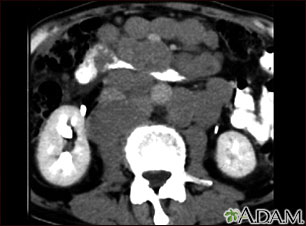

Esta TC abdominal muestra masas tumorales (linfomas malignos) en el área posterior a la cavidad peritoneal (espacio retroperitoneal).